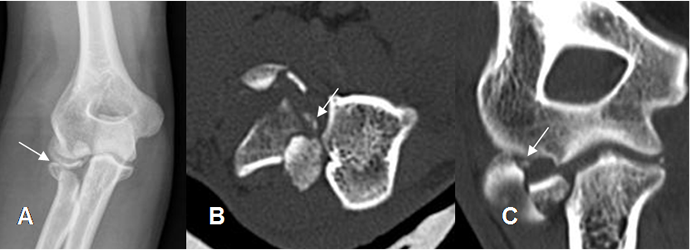

Fig 31. Fractura de codo, con cuerpo libre intra-articular.

A: Rx AP. Fractura en la cabeza del radio.

B: TAC axial. Fractura conminuta del radio, con varios fragmentos sueltos.

C: TAC reconstrucción coronal. Cuerpo libre intra-articular.